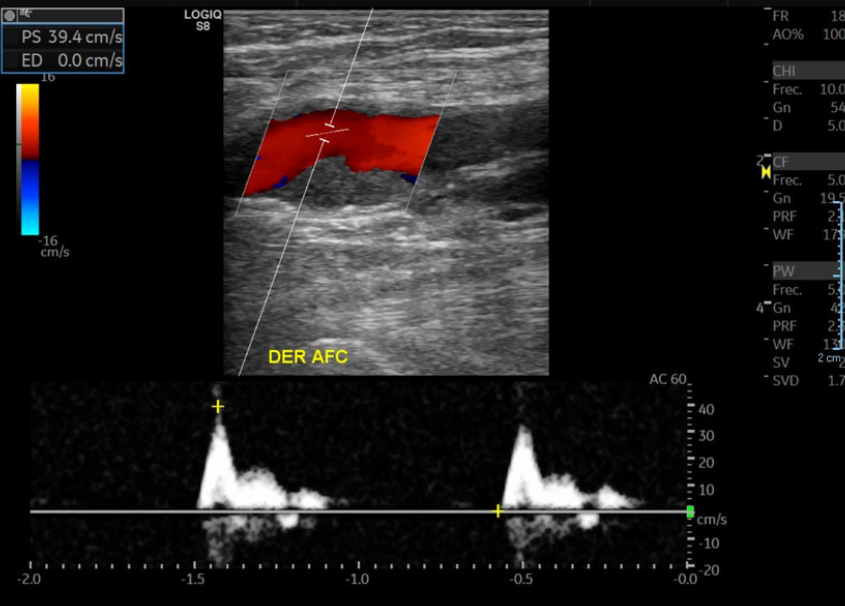

• Curvas arteriales de EEII DER con pérdida de su componente trifásico. Se observan con disminución de VPS habituales y con aumento de su TA.

• En relación AFC y AFP se observa extensa placa de ateroma hipoecoica y heterogénea que genera una estenosis significativa en AFP sobre el 75% con curvas tardus parvus posteriores en AFP.

Hallazgos: Con transductor lineal de alta frecuencia se explora el territorio arterial de la extremidad inferior derecha incluidas las arterias femorales común, femoral superficial, poplítea, tibiales anterior y posterior, peronea y pedia. Placas de ateroma calcificadas en todo territorio arterial de la extremidad inferior, con extensa placa a nivel de la arteria femoral común y profunda generando estenosis de aproximadamente 75% (aumento de velocidad peak sistólico desde 50 cm/s hasta 244 cm/s), con curvas espectrales de morfología parvus tardus en arteria femoral profunda distal a la estenosis. Oclusión completa de la arteria femoral superficial distal, con desarrollo de colaterales que permiten flujo hacia la arteria poplítea. Disminución de velocidad peak sistólico del resto de los vasos de la extremidad inferior, con curvas espectrales de morfología monofásica y parvus tardus. Incidentalmente, se observa aneurisma fusiforme de la aorta abdominal a nivel infrarrenal, en una extensión aproximada de 11.7 cm, con diámetro transverso de 7. 2 cm y anteroposterior de 6.9 cm, con prominente trombo mural que determinan gran disminución del lumen arterial.

Ateromatosis cálcica difusa de la extremidad inferior con extensa placa a nivel de la arteria femoral común y profunda generando estenosis de aproximadamente 75%. Oclusión completa de la arteria femoral superficial distal, con desarrollo de colaterales que permiten flujo hacia la arteria poplítea. Marcada insuficiencia arterial del resto de los vasos de la extremidad inferior. Voluminoso aneurisma fusiforme de la aorta abdominal a nivel infrarrenal, con prominente trombo mural que determinan gran disminución del lumen arterial. Es indispensable evaluación clínica y complementar estudio con AngioTAC de abdomen y pelvis y extremidades inferiores.